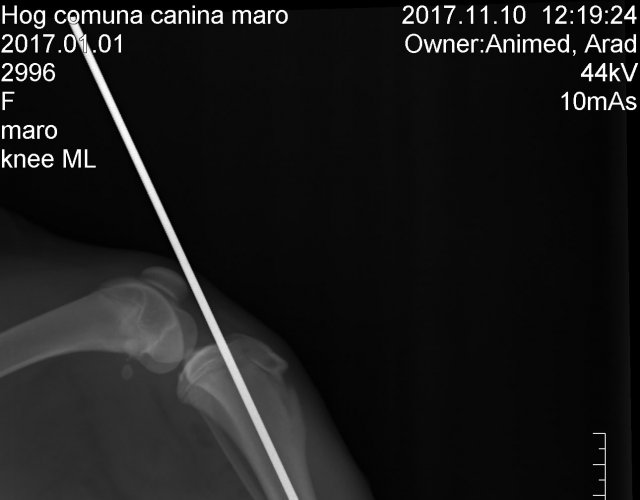

Catelusa aceasta s-a aciuiat pe langa o firma la care lucreaza un membru Animed. Am fost sunati pentru ca era evident ca este nevoie de asistenta medicala. Radiografia a aratat o fractura asa ca a fost operata.